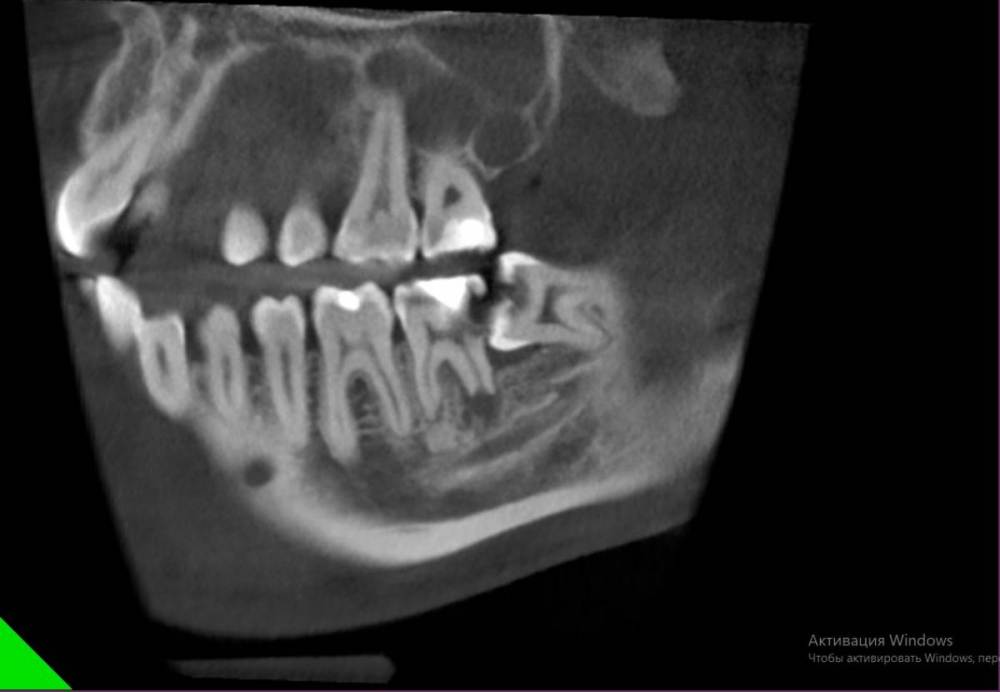

Анюсик Опубликовано 17 июля, 2021 Поделиться Опубликовано 17 июля, 2021 Добрый день! Ситуация такая, удалила ретенированнную дистопированную 8-ку.Она меня особо не беспокоила, просто за ней всегда скапливалась пища и прорезалась она с сильным насморком, я решила посмотреть, что там и сделала снимок, врач сказал что надо удалять иначе, могу потерять седьмой зуб. Я испугалась и согласилась на удаление. И если раньше меня ничего особо не беспокоило, то сейчас у меня появилась проблема: стала травмироваться слизистая над нижней 8-кой, там постоянная болячка и она как бы печёт и вообще мне как то дискомфортно без этого зуба. Врачи говорят, что надо удалять сейчас и нижний зуб, но он здоровый и ровный. Уже год так мучаюсь, помогите пожалуйста. 1.скажите, правильно ли я сделала, что удалила эту верхнюю левую 8-ку? 2.можно ли что то сделать без удаления нижнего зуба(отшлифовать 8 нижний, подвинуть 7-ку, она немного в щеку смещена, срезать капюшон над нижней 8 или может что то ещё)? Ссылка на комментарий

Irouil Опубликовано 18 июля, 2021 Поделиться Опубликовано 18 июля, 2021 (изменено) Ваши нижние восьмёрки не помещаются в челюсти. Анатомическая зона, в которой они расположены, очень опасна с точки зрения воспалительных процессов - тут они легко диссеминируют под челюсть и глубже, откуда достать их можно только разрезав шею. Учитывая примерно нулевую пользу от этих зубов в таком их положении, риски их оставления абсолютно неоправданны. Верхние же восьмёрки без нижних теряют даже теоретическую какую-то пользу, а так как реабилитация после удаления нижней восьмёрки чаще всего предполагает выраженный отёк на несколько суток - удаление верхней восьмёрки в такой ситуации проходит практически незаметно, чем большинство хирургов стараются пользоваться Изменено 18 июля, 2021 пользователем Irouil 1 1 Ссылка на комментарий

Sier10 Опубликовано 18 июля, 2021 Поделиться Опубликовано 18 июля, 2021 2 часа назад, Анюсик сказал: Какая была у меня ситуация? Вы можете более развёрнуто ответить? Пожалуйста. Просто мне уже другой врач сказал, что я могла и всю жизнь прожить с этим зубом. Ваша изначальная ситуация предрасполагала к вот такому исходу. Теперь вместе с зубом мудрости нужно удалять и соседний седьмой зуб. п.с. человека на снимке НИЧЕГО не беспокоило и не беспокоит. Забеспокоит только при обострении, изза чего при обращении нормально обезболить может не получиться, будет больно и тд и тп. Именно поэтому и рекомендуют в некоторых ситуациях превентивное (профилактическое) удаление зубов мудрости. Как и в вашем случае 1 1 1 Ссылка на комментарий